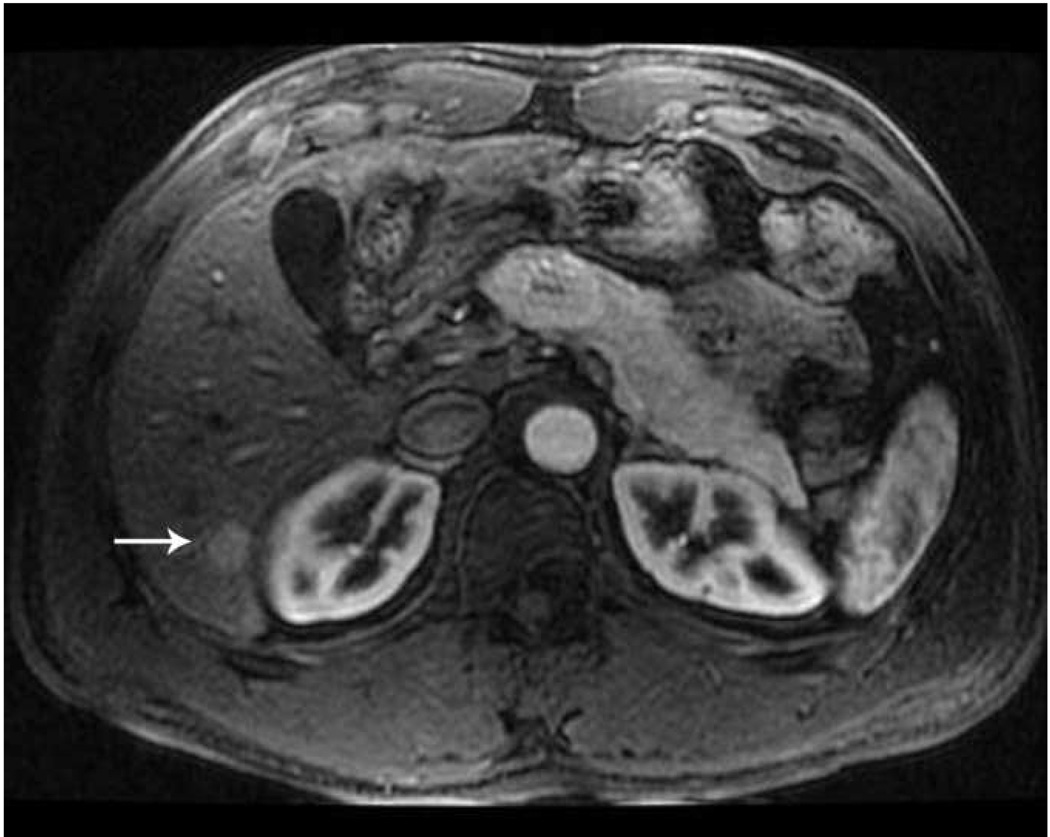

Kidney

The kidney is a highly vascular solid organ with high central perfusion rates creating significant heat sink effects (68). Combined with concern for damaging the renal pelvis and ureter, large or centrally located tumors can be difficult to treat with RF ablation (69). The improved ability of microwaves to overcome the cooling effects of blood flow enables production of larger ablation zones in the kidney, which has already been demonstrated in animal studies (70–72). Laeseke et al compared microwave ablation with high power triaxial antennas to RF ablation with similarly sized internally cooled electrodes in an in vivo porcine kidney model. Microwave ablation created significantly larger ablation zones with higher tissue temperatures (123 degrees C vs 100 degrees C) (70).

Early clinical studies have shown that microwave may be effective for the treatment of renal cell carcinoma (RCC). Clark et al operatively treated 10 patients with large renal tumors (3.9–13 cm in diameter) with up to three 13-gauge microwave antennas powered at 60 W for 10 minutes prior to radical nephrectomy. Pathology with viability stains demonstrated an average ablation zone volume of 105 cm3 (5.7 × 4.7 × 3.8 cm) when using a three probe array. An important additional finding was that there was uniform cell death in the ablation zone (73). Liang et al treated 12 patients with renal cell carcinomas (1.3–3.8 cm in diameter) with microwave and found complete ablation in a single session with no residual or recurrent tumor at a median follow up of 11 months (74). Although these preliminary results are promising, further clinical experience with the kidney is needed.